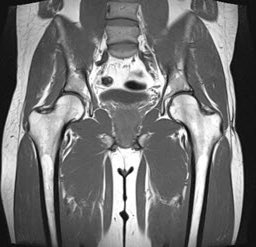

سأتحدث اليوم عن آلآم منطقة الورك الداخلي أو ما يعرف بالعامية ( #الصفاق ) لكثرة انتشارها لدى الرياضيين. (١)

آلآم الورك أو ما يعرف بالعامية ( الصفاق ) تكون في منطقة الحوض ولها أسباب وأعراض كثيرة تحتاج لتشخيص دقيق لمعرفة السبب. (٢)

المشاكل في منطقة الحوض قد تكون في:

يعاني ما يقارب من ٥-١٨ ٪ من الرياضيين من آلآم في الورك تحد وتقلل من نشاطهم الرياضي وتكثر في الرياضات التي تتطلب الركل ،الالتواء ، القفز. (٤)

وتكون في الغالب بسبب إصابات العضلات الضامة للورك ، في إحدى الدراسات لـ ٢٠٧ رياضي كانت لديهم إصابات في الورك الإصابات العضلية ٥٨٪ منها. (٦)

الفحص:

ويشمل الفحص والكشف السريري من خلال إجراء بعض الاختبارات اليدوية للعضلات والأربطة ومفصل الحوض وبالإضافة للأشعة التشخيصية. (١٢)